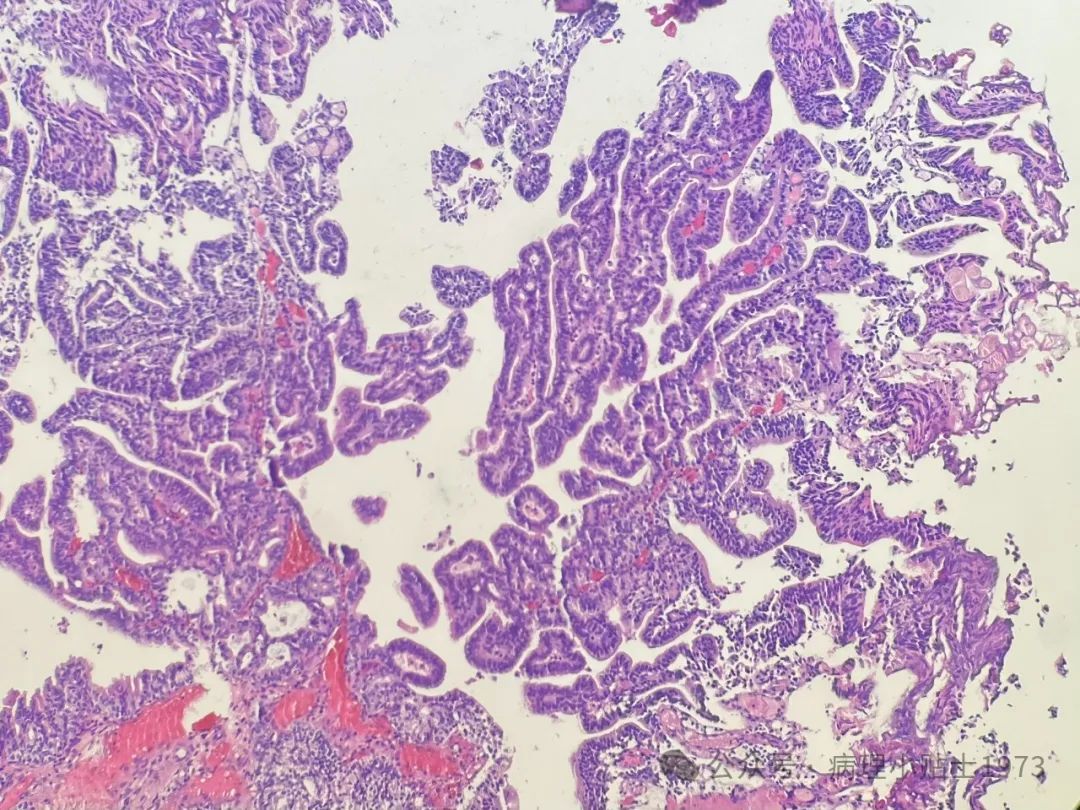

为了明确诊断,对患者膀胱内的病变组织进行了活检和病理检查。以下为显微镜下观察到的病理切片图像:

镜下观察显示,肿瘤呈现乳头状结构,符合尿路上皮癌的基本特征。但特殊之处在于,肿瘤组织中出现了显著的腺性分化区域。